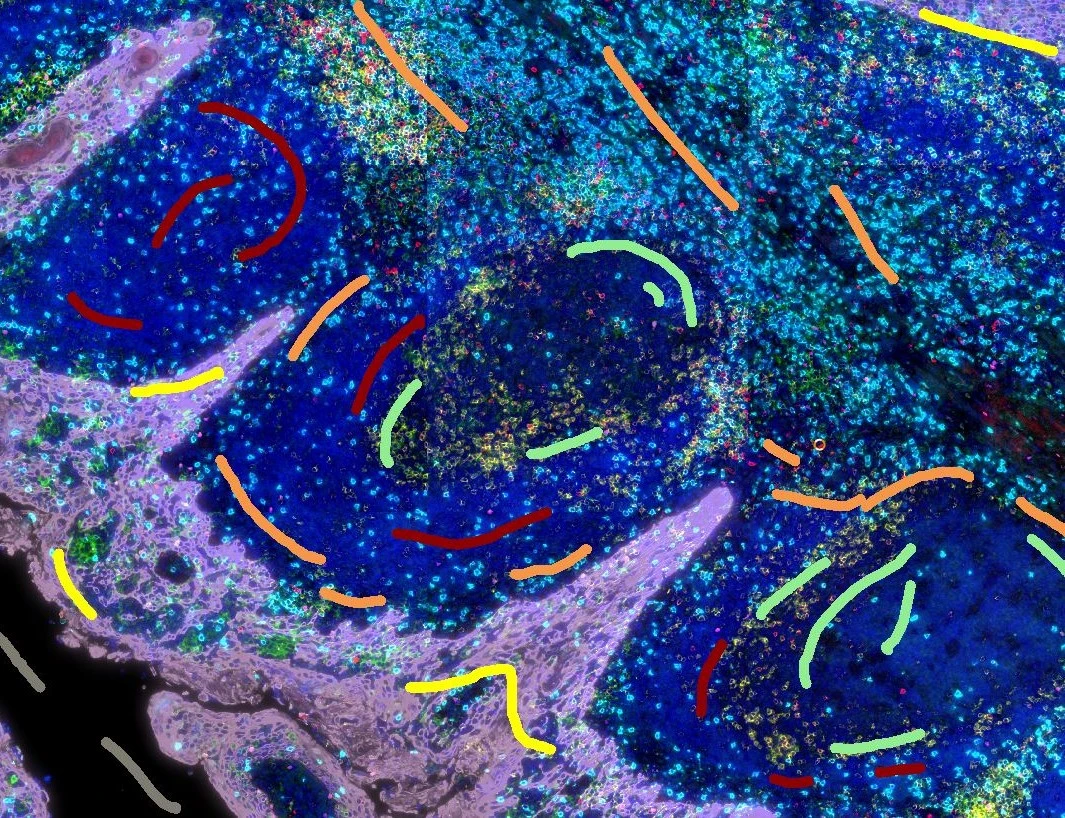

The Angio Sirius Red App detects collagen based on Sirius Red staining as well as blood vessels. As outcome the APP outputs the area of Sirius Red stained collagen as well as the number of detected vessels.

Original Image

vessel detection

Collagen detection